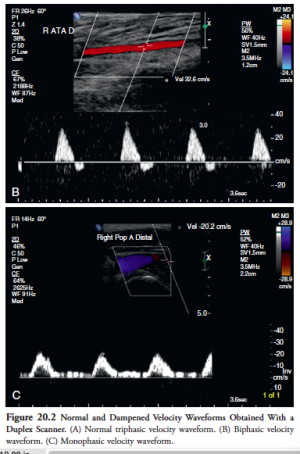

• Normal arteries a triphasic or biphasic quality, with brisk upstroke in systole, a brief reverse stroke in diastole (caused by the reflection of the flow wave from the high resistance periphery), and mostly a small forward component in late diastole

• When peripheral vascular resistance is low, the velocity waveform loses the reverse flow component and becomes monophasic with forward flow throughout the entire cardiac cycle

• Arterial obstruction causes dampening of the waveform which becomes monophasic